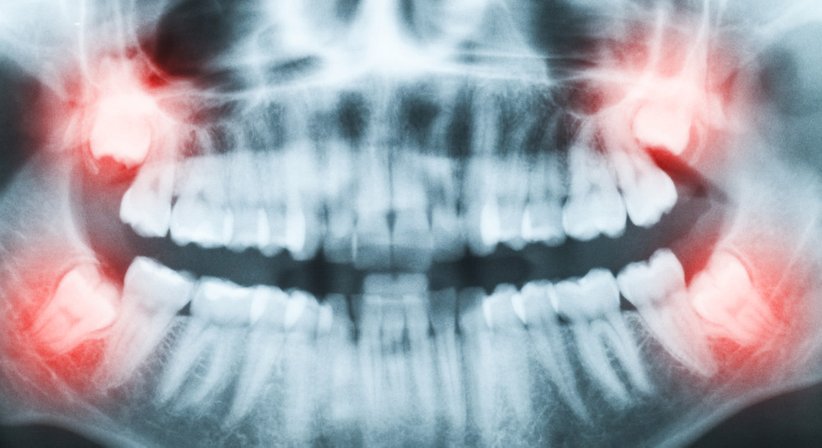

Bei einem unvollständig durchgebrochenen Weisheitszahn spricht man von einer Retention, während bei einem im Kieferknochen verbleibenden Weisheitszahn, der gar nicht durchbricht, von einer Impaktion gesprochen wird. Zudem können die Weisheitszähne auch verlagert (gekippt oder gedreht) im Knochen liegen.

Ein verlagerter oder retinierter Weisheitszahn kann die Gesundheit des Kiefers und zusätzlich die Stellung anderer Zähne beeinträchtigen. Zahnverschiebungen, Zahnfehlstellungen, schmerzhafte Zahnfleischentzündungen sowie die Bildung von Zysten und Abszessen sind die Folge. Des Weiteren können akute Infektionen auftreten. Auch Kariesbakterien haben ein leichtes Spiel.

Wenn der Weisheitszahn für eine der genannten Beschwerden sorgt ist es sinnvoll bzw. notwendig, ihn zu entfernen. Ein Weisheitszahn, der bei geradem Wurzelverlauf in die Mundhöhle durchgebrochen ist, kann in der Regel relativ einfach und vollständig gezogen werden. Sind die Zähne jedoch teilweise oder ganz im Kieferknochen eingeschlossen, müssen sie im Rahmen einer Weisheitszahnoperation entfernt werden. Dabei wird der betroffene Zahn freigelegt (das darüber liegende Zahnfleisch wird durch einen Schnitt geöffnet und vom Knochen gelöst) und, je nach Zustand und Lage, in einem Stück herausgelöst oder zerteilt. Nach vollständiger Entfernung wird die Wunde mit feinen Nähten verschlossen. Der Eingriff wird in der Regel ambulant unter Lokalanästhesie durchgeführt.